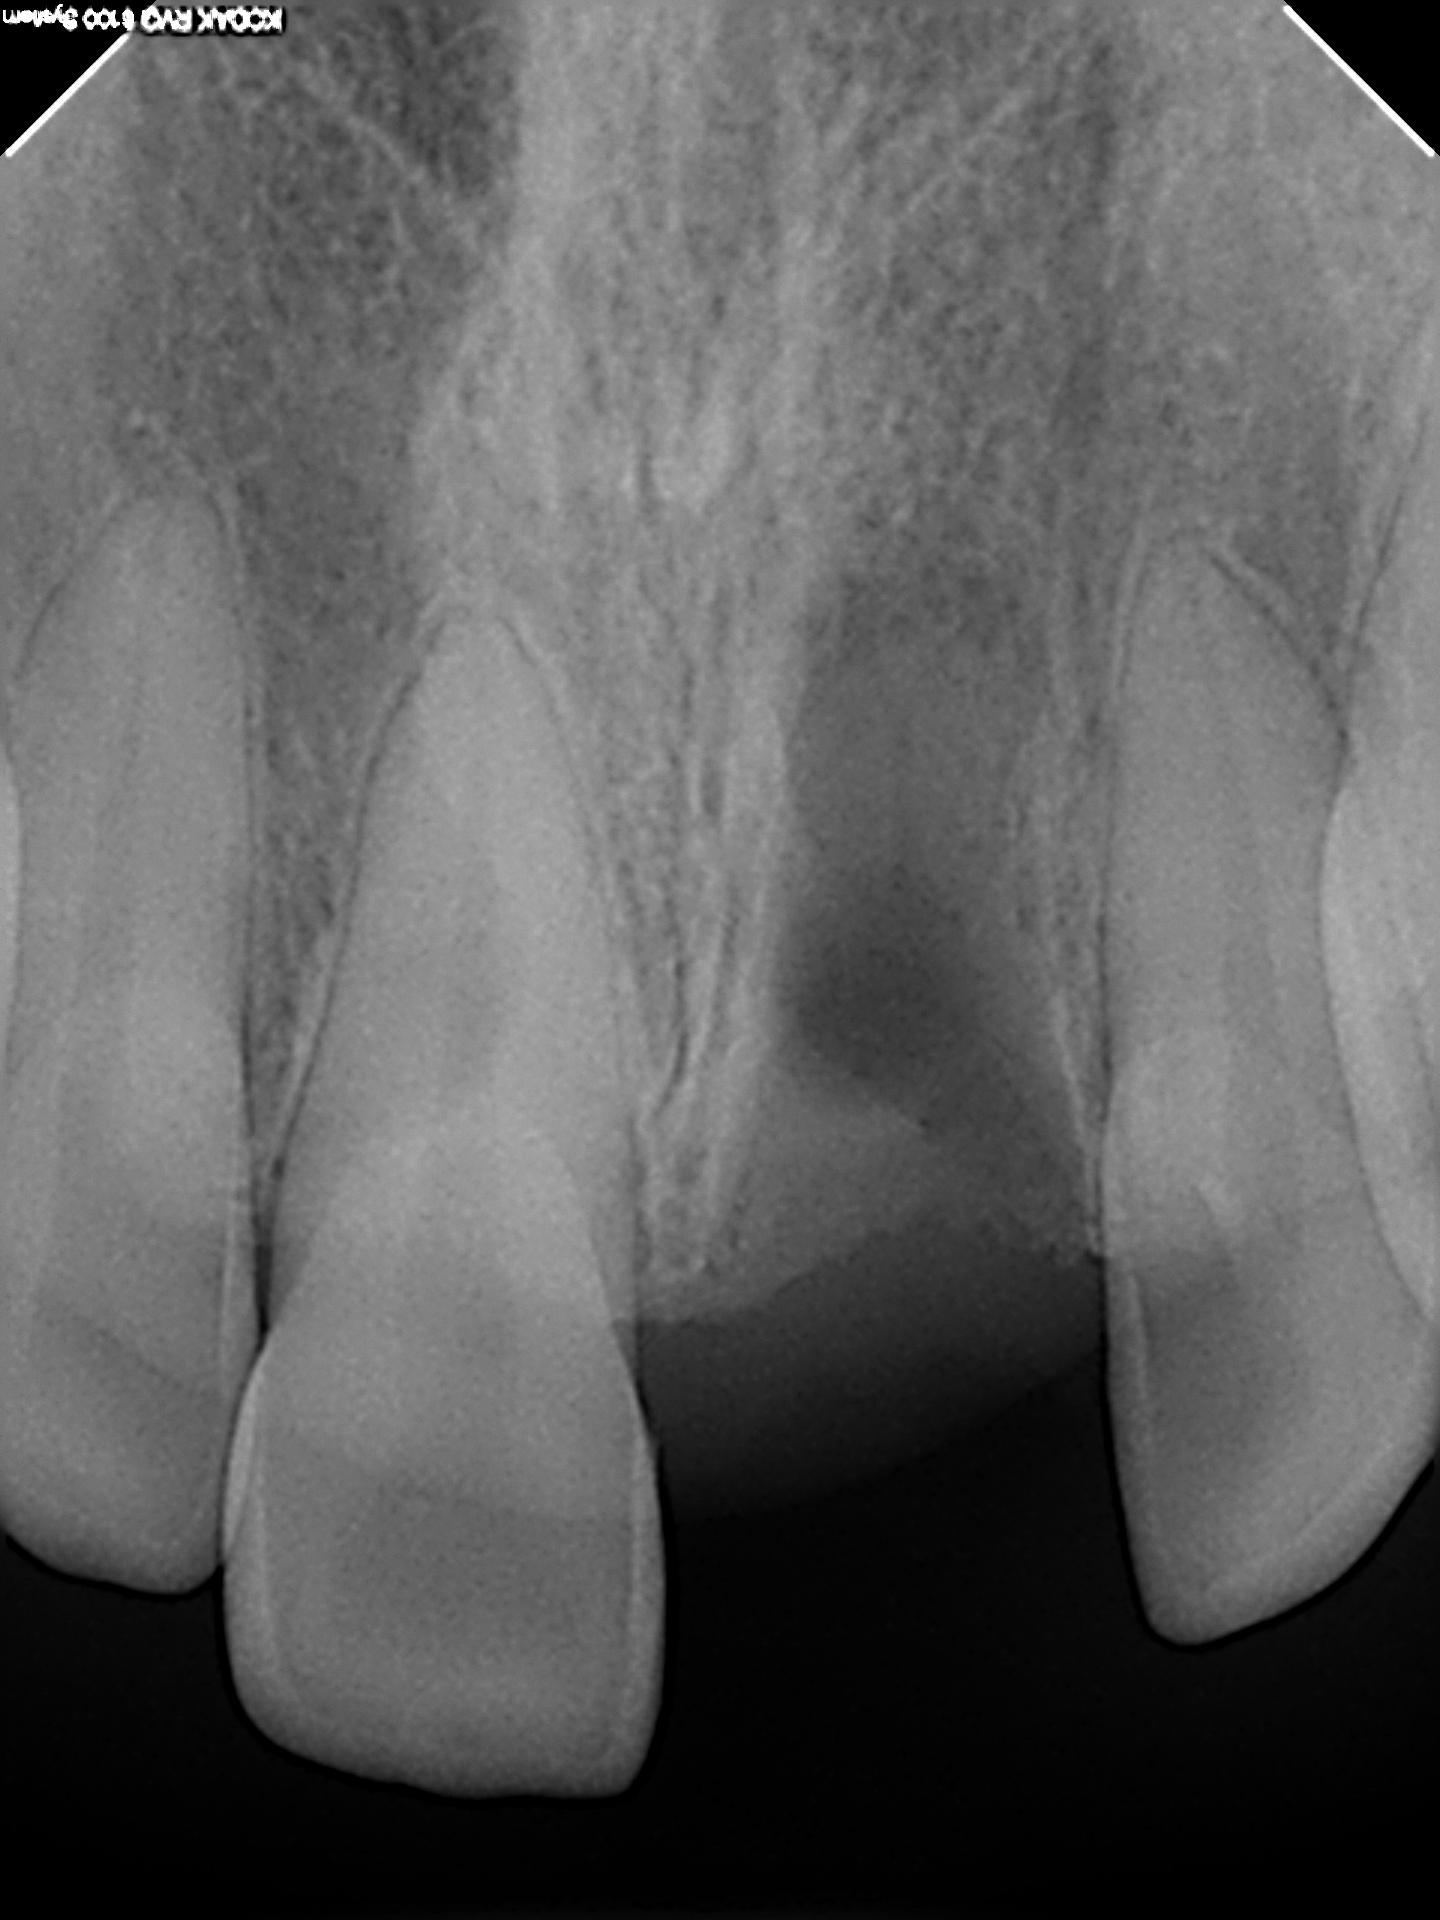

그중 선병원재단(이사장 선두훈) 선치과병원(원장 선경훈)은 세계적 기술력 보유를 목표로 지난 2013년부터 각종 첨단 장비를 설치 및 도입하면서 임플란트 진료시스템을 지속적으로 강화하고 있다. 먼저 임플란트 전 검사 단계에서는 3D 구강스캐너와 치과CT(Cone Beam CT)로 환자의 구강 상태를 정밀하게 진단한다.

구강구조와 턱뼈는 물론, 피부 밑 신경의 상태까지 확인할 수 있다. 뼈와 신경선에 대한 파악은 임플란트와 악안면수술의 성공률을 크게 좌우한다. 골밀도가 낮은 곳에 임플란트를 심거나 신경선을 잘못 건드리면 수술이 실패하거나 신경손상 같은 부작용이 발생할 수 있기 때문이다.